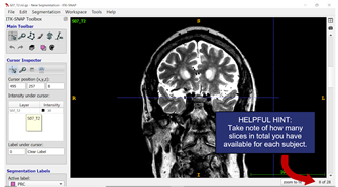

- Slice Numbers: When you scroll through the slices, the slice number at the bottom right corner increases as you from anterior to posterior in the brain (and you will segment from anterior to posterior).